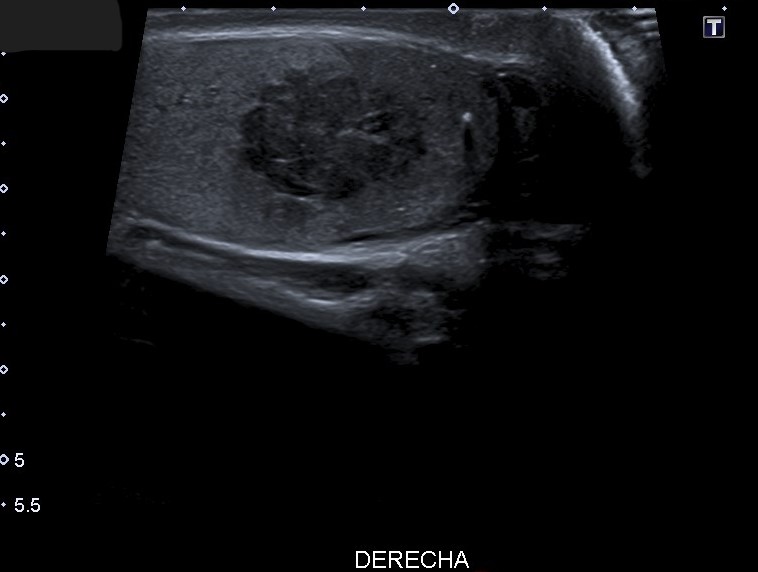

Hallazgos ecográficos

Ecografía escrotal: En testículo derecho se aprecia lesión heterogénea de predominio hipoecogénico con alguna calcificación grosera, polilobulada, de bordes mal definidos, con medidas aproximadas de 36 mm de diámetro máximo, con vascularización en su interior en el registro Doppler, sugestivo de proceso neoformativo testicular. No se objetiva engrosamiento epididimario ni de cubiertas escrotales.